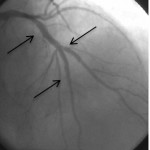

LAD damarı orta kısmında uzun, çatal iki yan damar çıkan, bir yan damarın girişinde de darlık olan kompleks darlık.